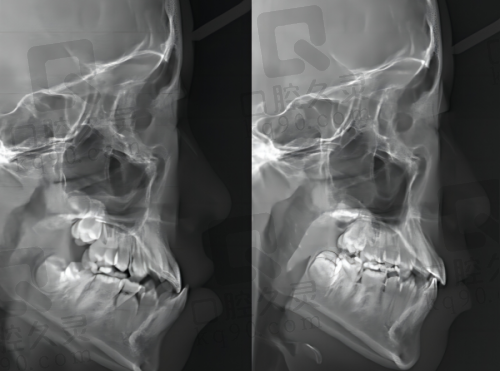

精良的设备和技术是正规口腔医院的重要标志之一。衢州蓝芽口腔引进了一系列国内外精良的口腔诊疗设备,如数字化口腔全景机、口腔CT等。这些设备能够为医生提供更加正确、详细的口腔影像资料,帮助他们更好地诊断病情。在治疗技术方面,医院采用了精良的牙齿矫正技术,如隐形矫正技术,这种技术具有美观、舒适、矫正成效好等优点,能够满足不同患者的需求。同时,在种植牙领域,衢州蓝芽口腔也采用了精良的种植系统和种植技术,大大提高了种植牙的成功几率和稳定性。精良的设备和技术为衢州蓝芽口腔的正规性提供了有力的支持。